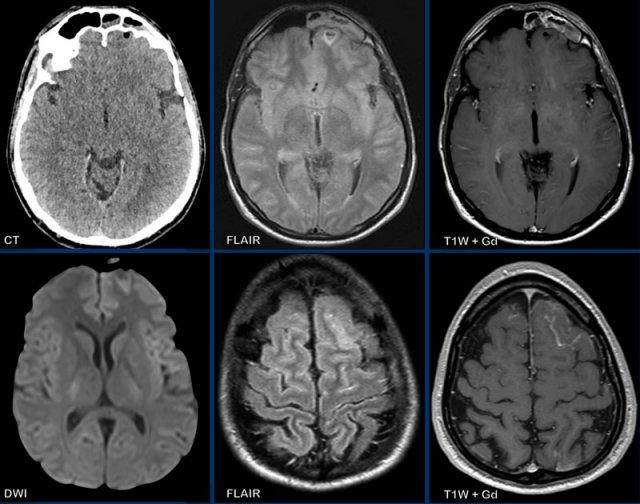

Các hình ảnh này của bệnh nhân 63 tuổi.

Hình ảnh

CT cho thấy tổn thương tăng tỷ trọng quanh não thất kèm phù não xung quanh.

Trên chuỗi xung T2W, tổn thương có tỷ trọng tương đối thấp. Tổn thương ngấm thuốc đồng nhất với nhiều tổn thương ngấm thuốc quanh não thất.

Tỷ trọng trên CT và phân bố tổn thương gợi ý mạnh đến u lympho.